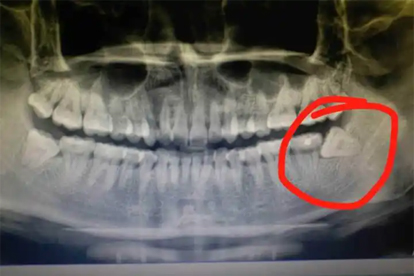

存在严重凝血功能障碍的患者不适合立即拔牙,如血友病或严重肝病患者,需要先治疗原发病改善凝血状态。智齿位置异常且已形成较大囊肿或肿瘤时,盲目拔除可能导致术中大出血,需影像学评估后制定周密手术方案。急性白血病引起的牙龈出血应视为拔牙禁忌,必须优先进行血液系统治疗。妊娠期妇女因激素变化导致的智齿周围炎出血,通常建议延期至分娩后再行拔除。颌骨内血管瘤等罕见病例在拔牙时可能发生危及生命的大出血,需要血管造影等详细检查后谨慎处理。

拔牙前应进行血液检查评估凝血功能,拍摄牙科锥形束CT明确智齿与邻牙及神经管的关系。炎症期需先进行局部冲洗上药和全身抗感染治疗,待急性症状缓解后再安排手术。术后需咬紧棉卷压迫止血,遵医嘱使用抗生素如阿莫西林胶囊预防感染。二十四小时内避免刷牙漱口和吮吸创口,进食温凉软食补充营养。保持口腔卫生但避免过度清洁手术区域,出现持续出血或剧烈疼痛需及时复诊。休息时适当抬高头部位置有助于减轻局部肿胀和出血倾向,恢复期间禁止吸烟饮酒以免影响伤口愈合。